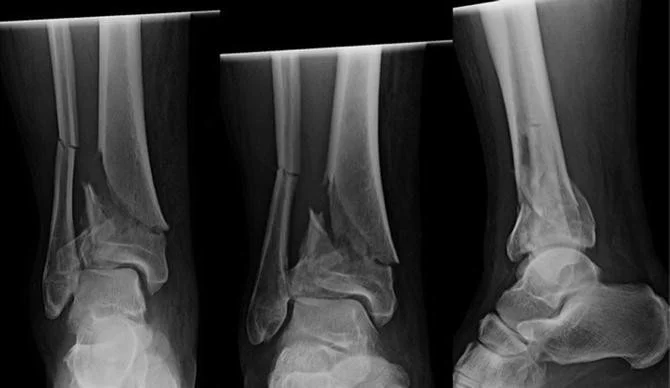

A pilon fracture is a complex fracture of the distal tibia involving the ankle joint surface. These injuries typically result from high-energy axial loading, where the talus is driven upward into the tibia, causing comminution and damage to the articular cartilage. Pilon fractures often involve significant soft-tissue injury and require careful, staged management.

The ankle joint relies on precise alignment and a smooth cartilage surface to function properly. In a pilon fracture, the distal tibial plafond is fractured, often into multiple fragments, disrupting joint congruity and stability. These fractures frequently occur in combination with fibular fractures and severe swelling or soft-tissue compromise.

Imaging plays a central role in diagnosis. X-rays are used to identify fracture patterns and alignment, while CT scans are routinely obtained to evaluate the extent of joint surface involvement and to assist with surgical planning.